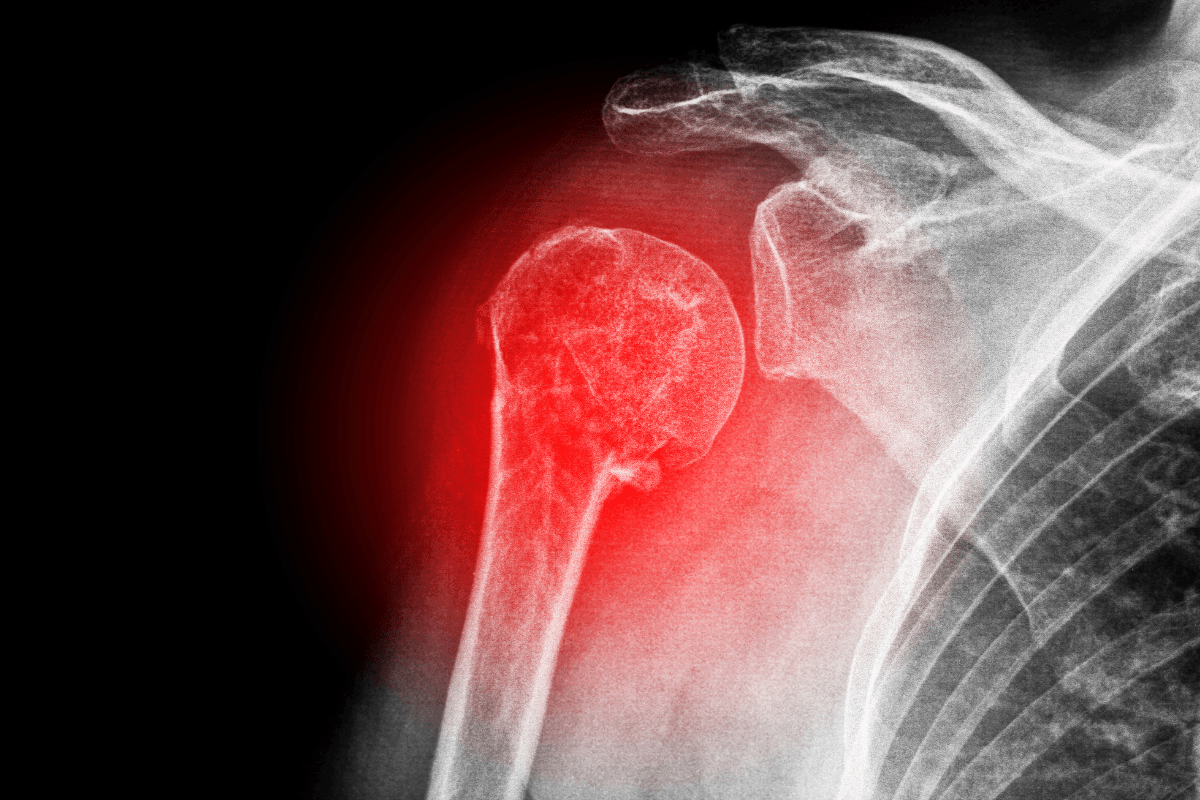

Shoulder Replacement

We provide total, partial, and reverse shoulder replacements for arthritis or post-traumatic damage, restoring joint motion and relieving chronic shoulder pain.